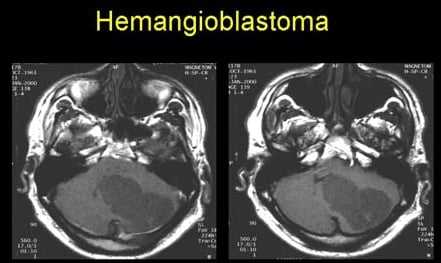

В 60% случаев гемангиобластомы представляют собой четко отграниченное гомогенное образование содержащее кисты с не усиливающимися стенками, муральный узел активно усиливается [2]. Нередко сам муральный узел имеет внутри кисты. Солидные узлы обычно примыкают к мягкой мозговой оболочке.

Магнитно-резонансная томография

- T1

- гипо- и изоинтенсивный муральный узел

- сигнал от содержимого кист идентичный сигналу ЦСЖ

- муральный узел имеет выраженное контрастное усиление [2,4]

- стенки кист не усиливаются [4]

- гиперинтенсивный муральный узел

- феномен пустоты потока за счет расширенных сосудов, особенно в периферических кистах, встречается в 60-70% случаев [4]

Радиологические находки

В 60% случаях гемангиобластома — это однородное образование с четкими контурами, стенки которого не контрастируются. Однако, муральный узел контрастируется, если опухоль представлена вторым патоморфологическим вариантом.

- гипоинтенсивный/изоинтенсивный муральный узел

- киста с жидкостным содержимым

- муральный узел контрастируется

- стенка кисты не контрастируется

- Кисты, заполненные жидкостью

- Расширенные сосуды по периферии образования